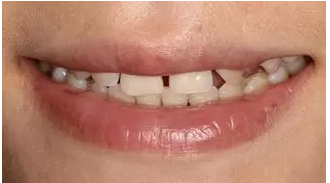

術前微笑照

病例分享|復合樹脂微創(chuàng)美學修復關閉上前牙間隙

術后微笑照

術后1 周復診